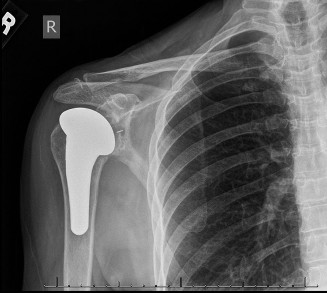

-

[Post-operative radiograph demonstrating well-fixed total shoulder arthroplasty components.]